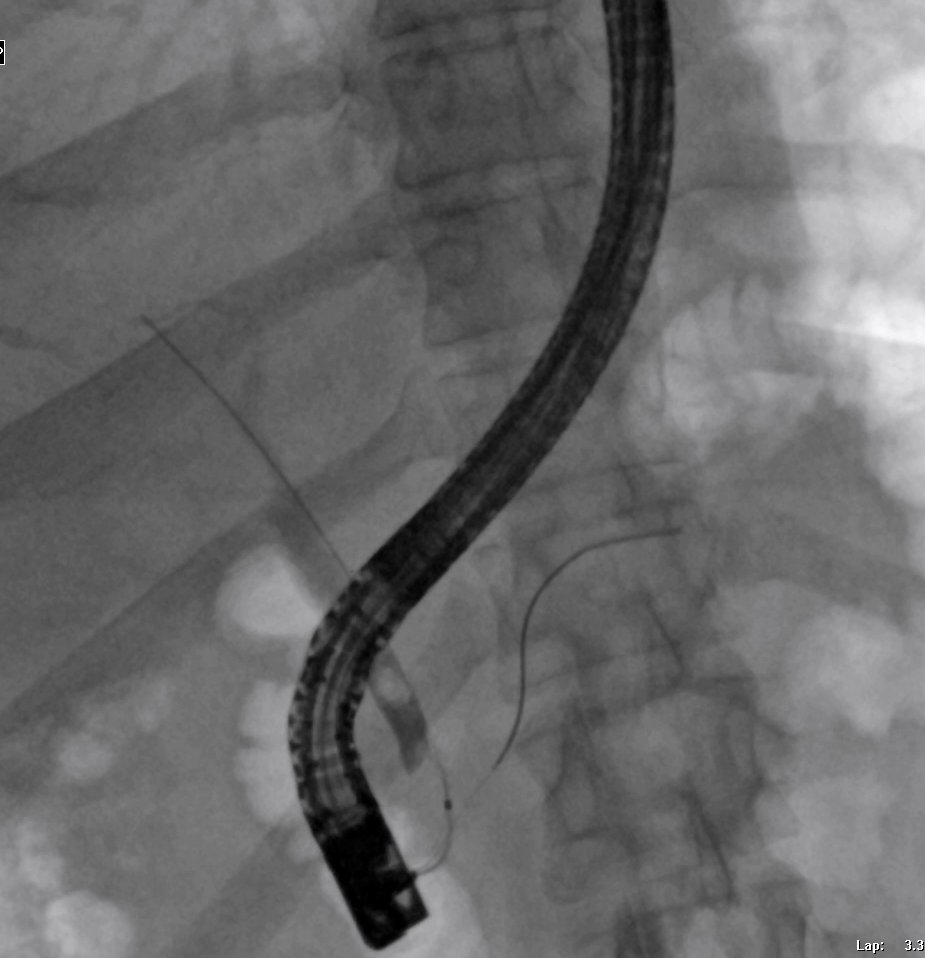

🔴Single-session laparoscopic cholecystectomy and ERCP; Great cooperation with my colleague ⭐️ surgeon @alherz_fadhel and his outstanding efforts to adopt such an approach in a great facility.

✅️Single-session ERCP and LC are safe, effective, economically viable, and reduce hospital stay compared with performing ERCP and LC during separate sessions. Most importantly, it's linked to minimising the risk of pancreatitis as there is no manipulation with the papilla Directly with the rendez-vous approach and before that one-day procedure.

➡️I think it's deserved for multi-centre studies to assess the efficacy of such an approach and how to overcome the logistics...There are a couple of studies in the past...

Interested to know the Thoughts from different practices; if you have a surgeon willing to do with logistics support, nursing, time, etc, do you stand with such an approach, or do you prefer to do ERCP solely?